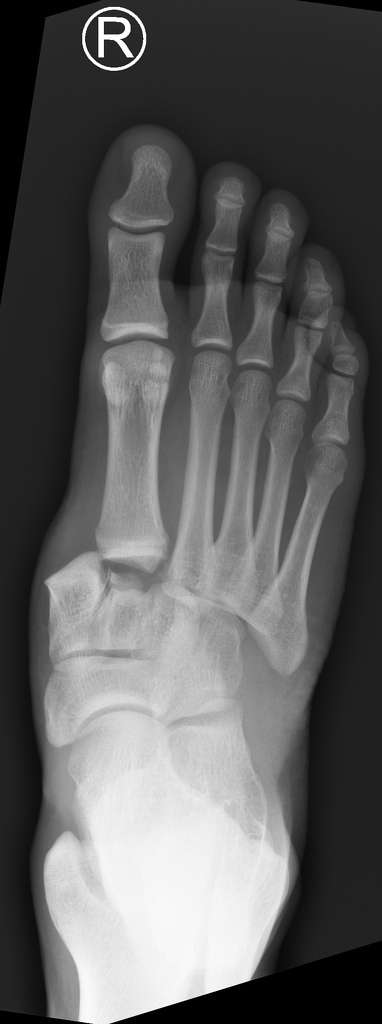

Lisfranc-Gelenk (tarsometatarsales Gelenk, gelbes Oval) einer 70-jährigen Patientin mit Arthrose im Röntgenbild. © Gelenk-Klinik

Tarsometatarsale Fraktur/Lisfranc-Fraktur im Röntgenbild: In diesem Bild sind die Fußwurzelgelenke disloziert, also nicht mehr in der normalen anatomischen Position. Das ist eine sichere Indikation zur Operation. © Case courtesy of Dr. Andrew Dixon, Radiopaedia.org

Röntgenaufnahmen der Füße in zwei Ebenen zeigen mögliche Arthrosezeichen in der Fußwurzel: Gelenkspaltverengung und Osteophyten (Knochenanbauten).